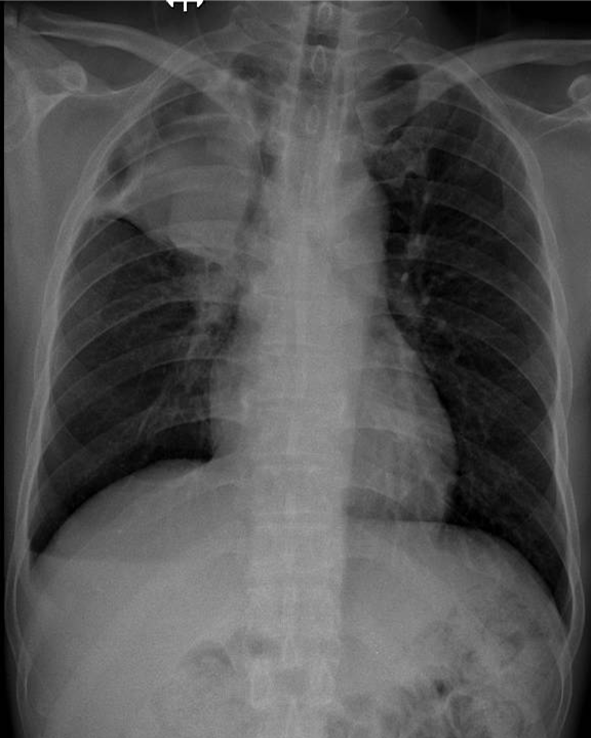

Hãy phân tích tình huống Nữ 54 tuổi -CĐ:Tràn dịch màng phổi (P) lượng nhiều nghi do lao

1-Khí quản lệch (T) 2-Tràn dịch màng phổi (P) lượng nhiều 3-Bóng tim và trung thất lệch (T)